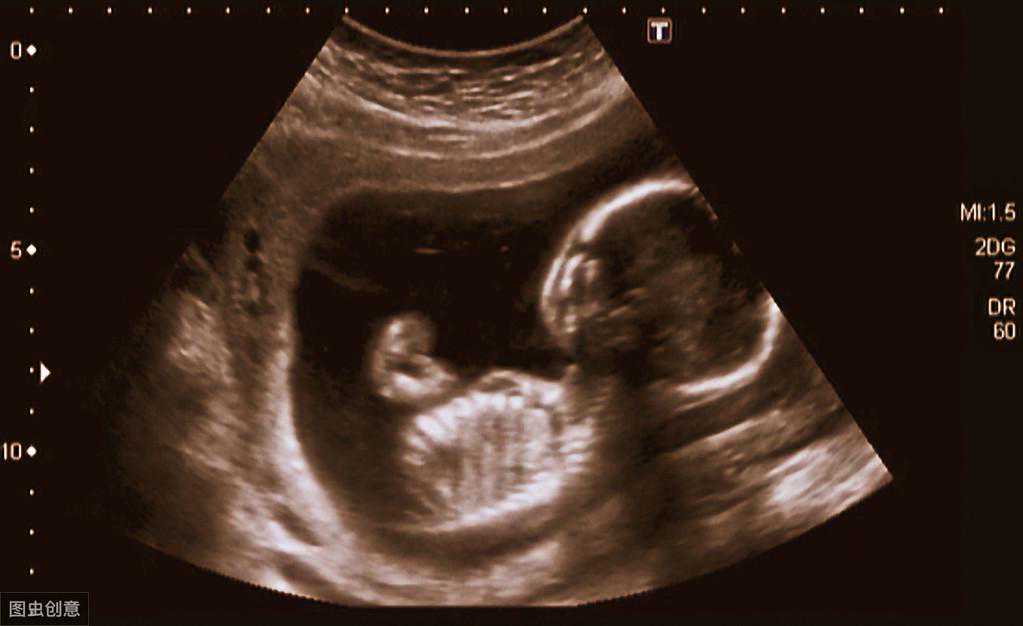

怀孕4个月(16周末)的胎儿的各项发育指标如下:

双顶径:3.62±0.58厘米

腹围:10.32±1.92厘米

股骨长:2.10±0.51厘米

头围:12厘米

体重:约110g

身长:约16厘米

孕妈妈们也可以对照自己的B超检查结果,查看胎儿的发育情况,是否都在正常范围内,有疑问要及时咨询医生。